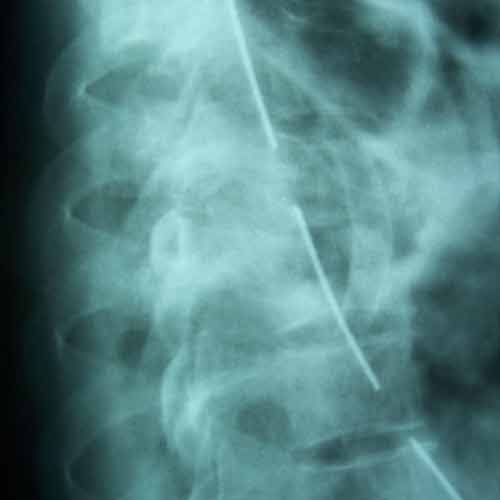

Post-op X-ray Lateral